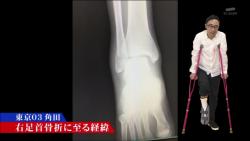

今まで12か所折った石田さんの骨折の歴史をたどる。

肋骨は体をひねっただけで折れた。

デコピンをしたら指の骨が折れるw